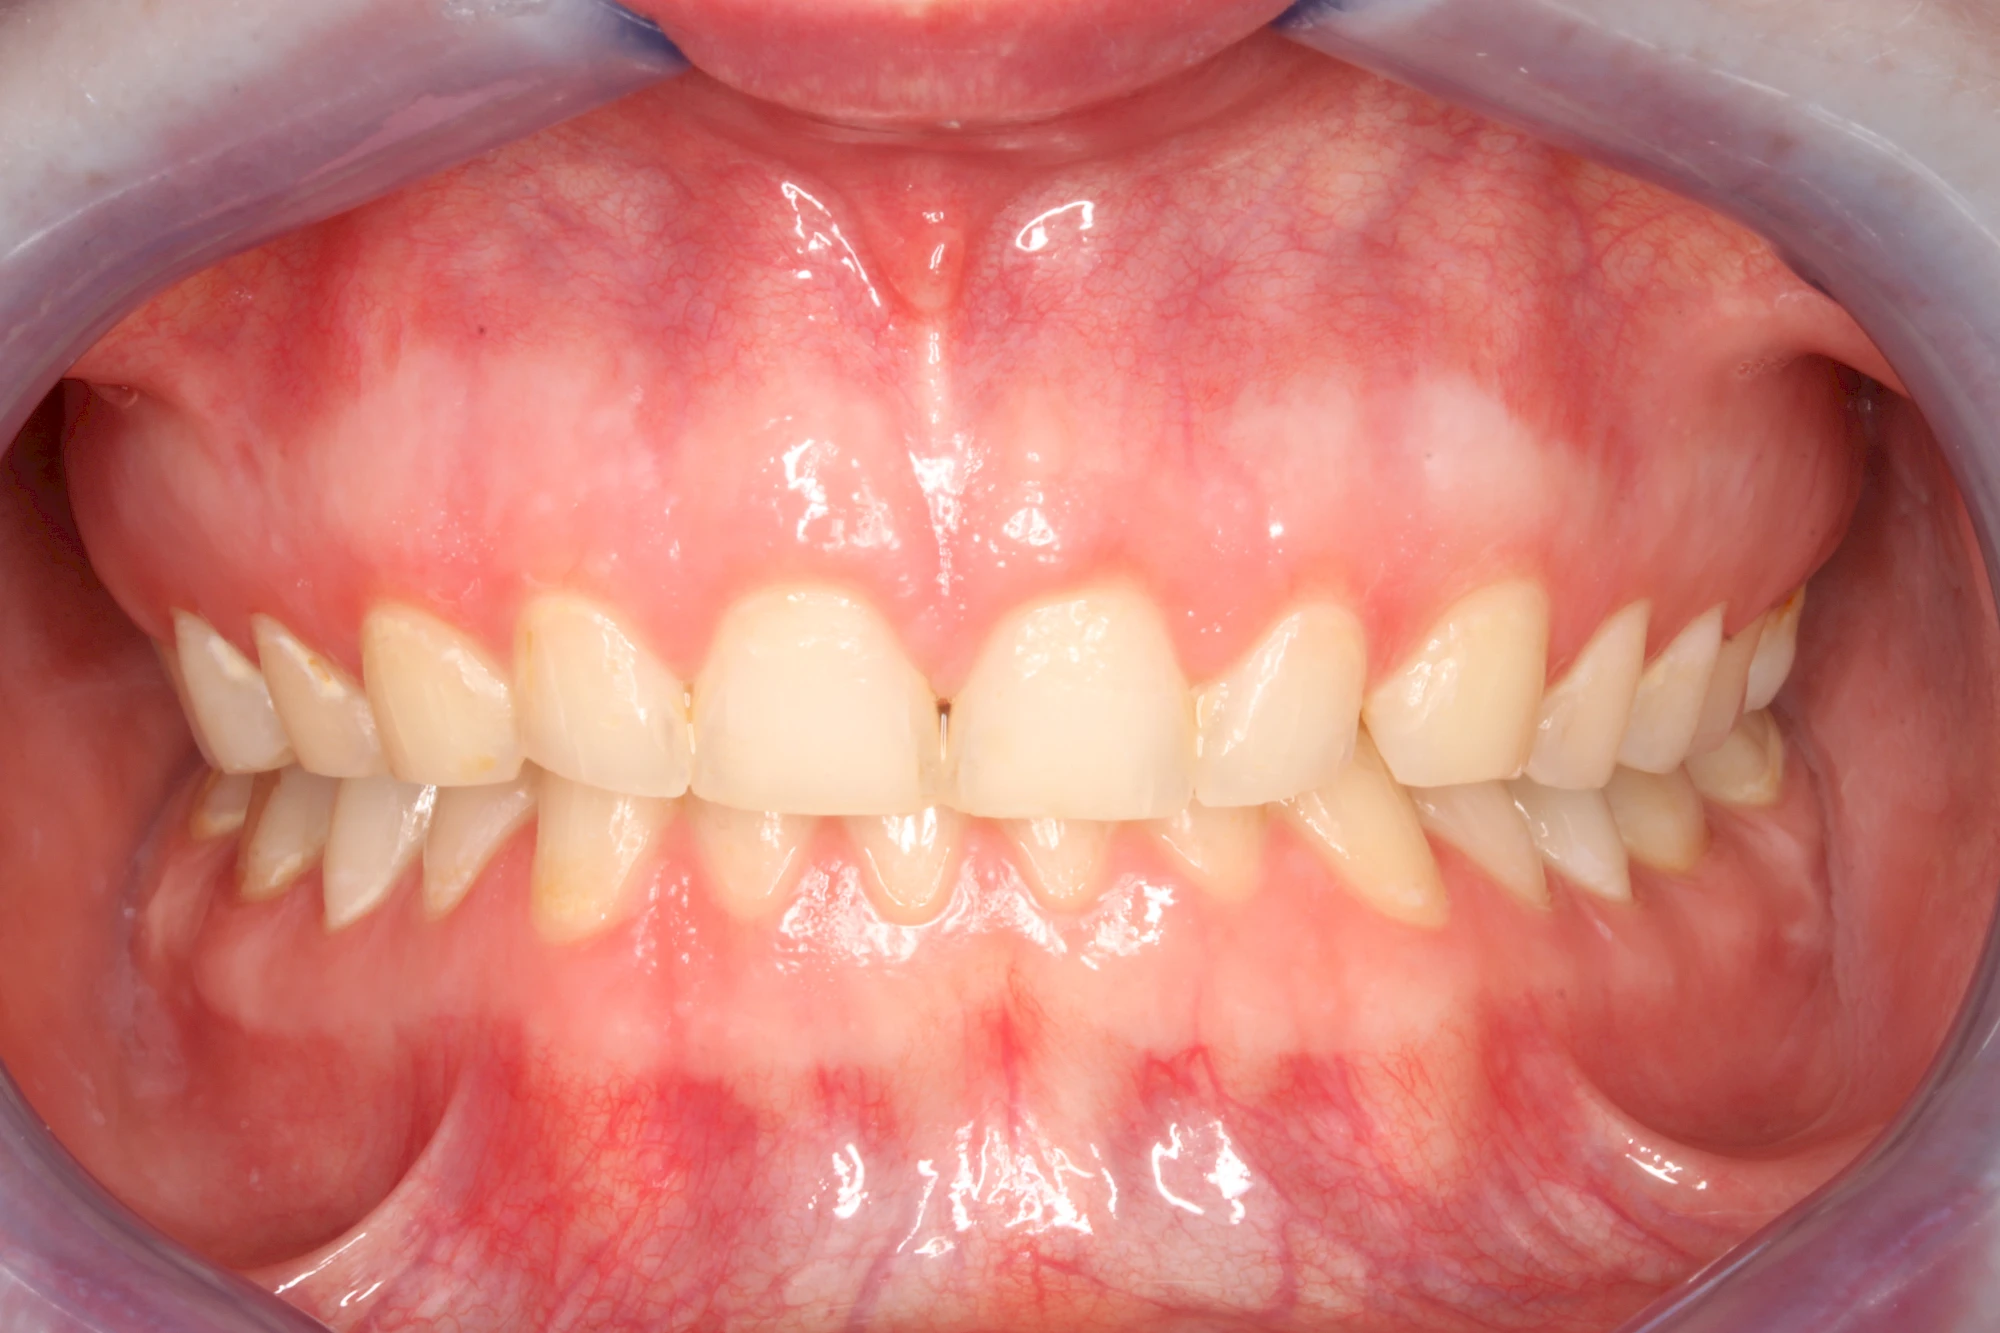

Über die Zeit können verschiedene Prozesse die Zahnhartsubstanzen aufzehren:

- Abnutzung durch Kauen (Abrasion) oder duch durch übermäßiges Knirschen bzw. Pressen (Attrition)

- Säurebedingte Auswaschung (Erosion)

Die Zähne können dabei auf Reize (warm, kalt, süß, sauer) oder auch beim Zähneputzen empfindlich oder schmerzhaft sein. In allen diesen Fällen ist es sinnvoll, den Zahnarzt zu kontaktieren und das weitere Vorgehen abzustimmen.

Auswaschung (Erosion) dagegen ist eine Verschleißerscheinung der Zähne aufgrund von immer wiederkehrenden Säureangriffen durch die Nahrung, verstärkt zum Beispiel durch den Genuss säurehaltiger Getränke oder Speisen. Auch bei Menschen mit einer Essstörung (z. B. Bulimie) können die Zähne durch die Magensäure ausgewaschen erscheinen.